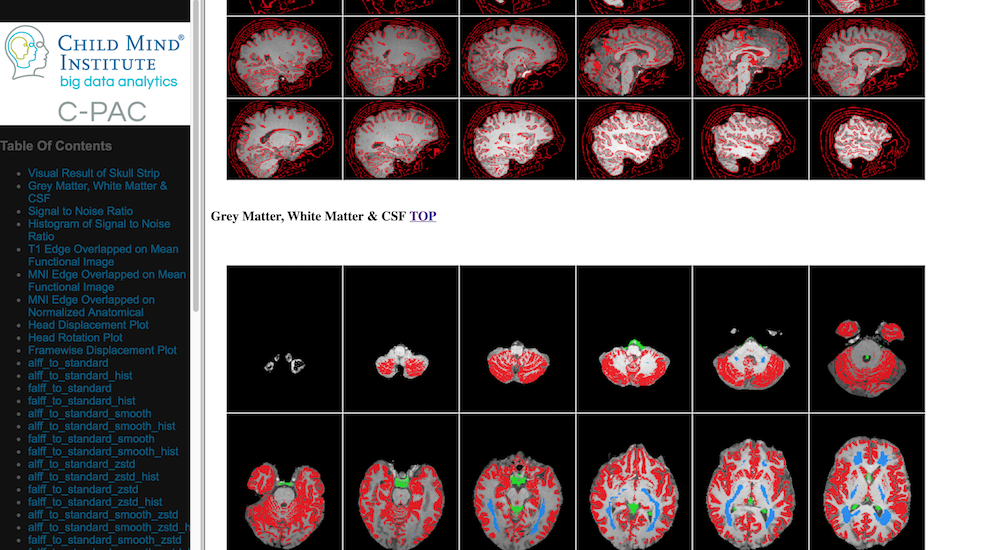

Visual Quality Control

C-PAC’s data quality control (QC) interface allows you to take a quick glance at the overall quality of your results (registration quality, signal-to-noise ratio, movement plots, computed derivative histograms, etc.). In its current form, the QC interface is a collection of HTML pages - one for each participant-scan-nuisance regression strategy combination, and they can be found in the Output Directory under each participant’s directory level.

Skull-stripping and Segmentation Quality

../_images/qc_interface1.png